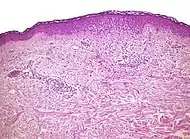

Micrograph of a vacuolar interface dermatitis with dermal mucin, as may be seen in lupus. H&E stain.

| Lupus erythematosis | Typical findings in systemic lupus erythematosus:[4]